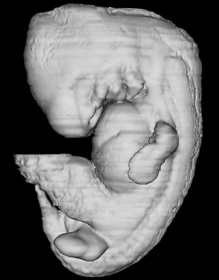

Keywords: alar plate(s), artifact separation(s), basal plate, cephalic edge of vestibular part of otic vesicle, endolymphatic duct, isthmus of rhombencephalon, mesencoel (cerebral aqueduct), rhombencoel (fourth ventricle), roof plate, sulcus limitans, vascular plexus

Source: The Virtual Human Embryo.